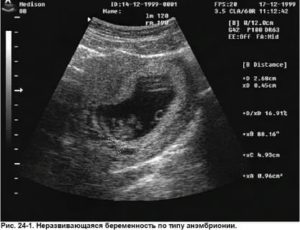

- Эмбрион не был обнаружен, хотя размеры плодного яйца более 20 мм. В этом случае ставится диагноз анэмбриония. При нормальном течении беременности уже на 7-й неделе размеры эмбриона достигают 20 мм;

Существует также состояние под названием анэмбриония, которое характеризуется полным отсутствием плода. На ультразвуковом исследовании будет установлено, что плодный пузырек пустой, это встречается на 4-5 неделе.